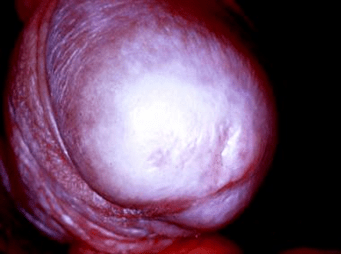

Balanitis Xerotica Obliterans:

Balanitis xerotica obliterans (BXO), known as lichen sclerosus, is an infiltrative skin condition that causes a true phimosis and a clinically recognizable lesion at the tip of the prepuce. It is usually distinguished by a ring of hardened tissue with extensive scarring, a whitish color at the tip of the foreskin, and edema. It has been said to be a common underlying cause of persistent nonretractability of the foreskin at puberty, while the overt lesion is rarely seen in children under 5 years of age. However, BXO was found in 15% of children undergoing circumcision for phimosis. Presentation is with inability to retract the prepuce, discomfort after micturition, and occasional minor obstructive signs. The preferred treatment for BXO has been circumcision, which will remove all the affected tissue. Preputioplasty is not an option because the continuing inflammatory process results in recurrent stenosis of the preputial orifice. Remaining lesions on the glans nearly always regress or resolve following circumcision. Meatotomy or meatoplasty is needed in cases of severe meatal involvement,and postoperative application of topical steroid may lessen the risk of subsequent restenosis.